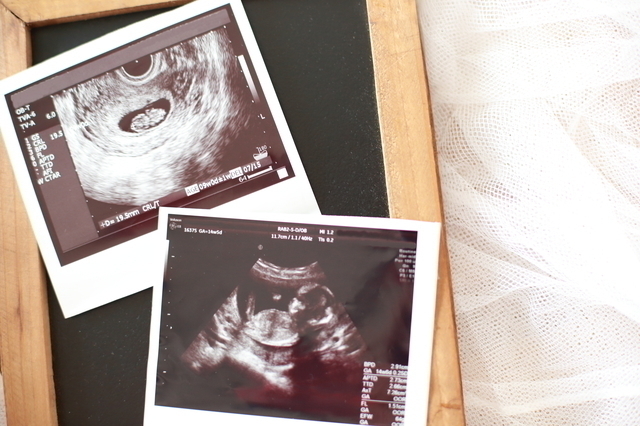

この頃の超音波診断では、すっかり人間らしい姿に成長した赤ちゃんが確認できるようになります。まだ10cmにも満たない小さな体ですが、元気に動くようになります。

羊水の中でピョン!と動いたり、手足を動かしたりする場面に出会えるかもしれません。記念に貰えるエコー写真が楽しみになってくる時期ですね。